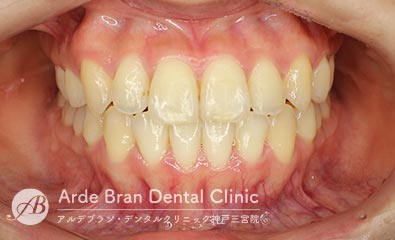

- 叢生/歯のがたつき(20代男性 治療期間10カ月)

- 上下の前歯の歯のがたつきを治したいとの事でご来院されました。なるべく目立たない装置をご希望されたため、インビザラインにて治療を行いました。中等度の叢生量だったため、インビザラインモデレート(枚数26枚)にて治療を行う事が出来ました。短期間で費用も可能な限り抑えつつ治療を完了する事が出来ました。

- 治療前

- 治療後

| 装置名 | インビザライン(マウスピース矯正) |

| 抜歯非抜歯 | 非抜歯 |

| 治療期間 | 10カ月 |

| 費用 | インビザラインモデレート(上下)60万円+TAX 再印象(3万円+TAX)×1回 |

| リスク副作用 | 装置装着による違和感、歯の移動時の痛み、歯根吸収など。詳しくはこちらをご参照ください。 |